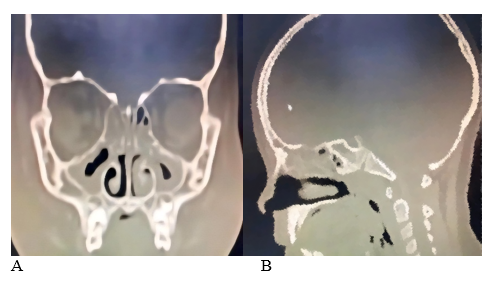

After 72 hours, the periorbital inflammation improved, and the patient underwent FESS under general anesthesia. During the procedure, a bilateral antrostomy and ethmoidectomy were performed. Mild purulent material was drained from the right anterior ethmoid sinus. Unexpectedly, several polyps were identified and removed endoscopically from the roof of the right ethmoid cavity (Figure 2). The excised polypoid tissue was submitted for histopathological examination. Hemostasis was verified, and intranasal irrigation was performed; bacitracin was applied instead of anterior nasal packing to optimize patient comfort and recovery. The histopathological report describes fragments of a polypoid lesion lined with respiratory epithelium. The subepithelial stroma is loose and edematous, containing an inflammatory infiltrate composed of lymphocytes, plasma cells, eosinophils, neutrophils, and mast cells (Figure 3). The final diagnosis was ethmoid polyposis associated with chronic rhinosinusitis and allergic rhinitis, resulting in a satisfactory postoperative outcome and symptom improvement within the first week. Postoperatively, the patient was managed with nasal saline rinses, intranasal corticosteroids, and oral antihistamines. She was discharged with significant symptom improvement. She remains symptom-free at 24 months.

Figure 2 A; Pus drainage, B; Right ethmoid cavity roof polyps.